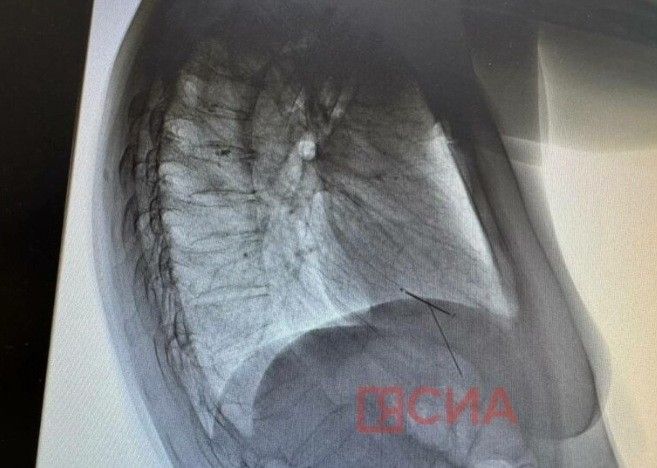

Игла в мышце сердца находится там уже пару лет. Пациентка обратилась в больницу после второго случая. На этот раз игла оказалась в левом легком. Операцию провел заведующий хирургическим отделением Якутской больницы ФГБУЗ ДВОМЦ ФМБА России, врач-хирург Айсен Васильев, приехав в командировку в Верхневилюйскую ЦРБ.

«Игла проникла под кожу и задела левое легкое. Инородное тело извлекли через маленький разрез под общим наркозом. Операция прошла успешно, компьютерная томография показала четкое расположение игл. Состояние пациентки удовлетворительное, она готовится к выписке», – рассказал Айсен Васильев.

«Игла в сердечной мышце находится уже несколько лет. В архивных документах мы нашли рентген 2023 года, где инородное тело уже было там. По словам пациентки, игла её не беспокоит. Сейчас идет консультация с Кардиоцентром», – добавил врач-хирург.